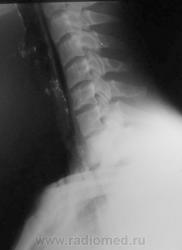

Молодой человек получил удар в шею. Был доставлен в травмпункт, дан барий для исключения перфорации пищевода.

Перфорации похоже нет, но есть другое...

Это чем же его ударили? Я так понимаю, ограниченный пневмоторакс слева  + эмфизема мягких тканей шеи?

Шейный кифоз настораживает.Отсутствие легочного рисунка в верхней доле левого легкого с краем легкогоЭмфизема мягких тканей шеи..Согласна с коллегой.Пару лет назад по кифозу ШОП, увеличению превертебрального пространства и столбу воздуха поставили разрыв пищевода.Дали  контраст-подтвердили.

Затекания контраста за пределы пищевода на представленных рентгенограммах не выявлено. Нет фазы тугого заполнения. Левосторонний пневмоторакс.

Да, ЛОРа 100% надо на консультацию, т.к. барий затек не туда.